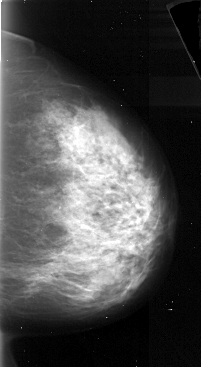

A_1072_1.LEFT_MLO

LEFT_MLO LINES 5326 PIXELS_PER_LINE 2716 BITS_PER_PIXEL 16 RESOLUTION 42 OVERLAY